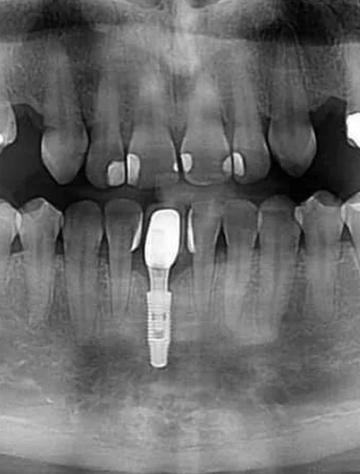

- 种植体位置: 确认种植体是否放置在理想位置。

- 骨结合情况: 观察种植体与周围骨组织是否良好结合(骨整合)。

- 专业口腔CBCT: 这是种植牙评估的首选,它的扫描范围小、分辨率高(尤其是骨组织)、金属伪影相对可控,能提供种植区域最精细的3D图像。